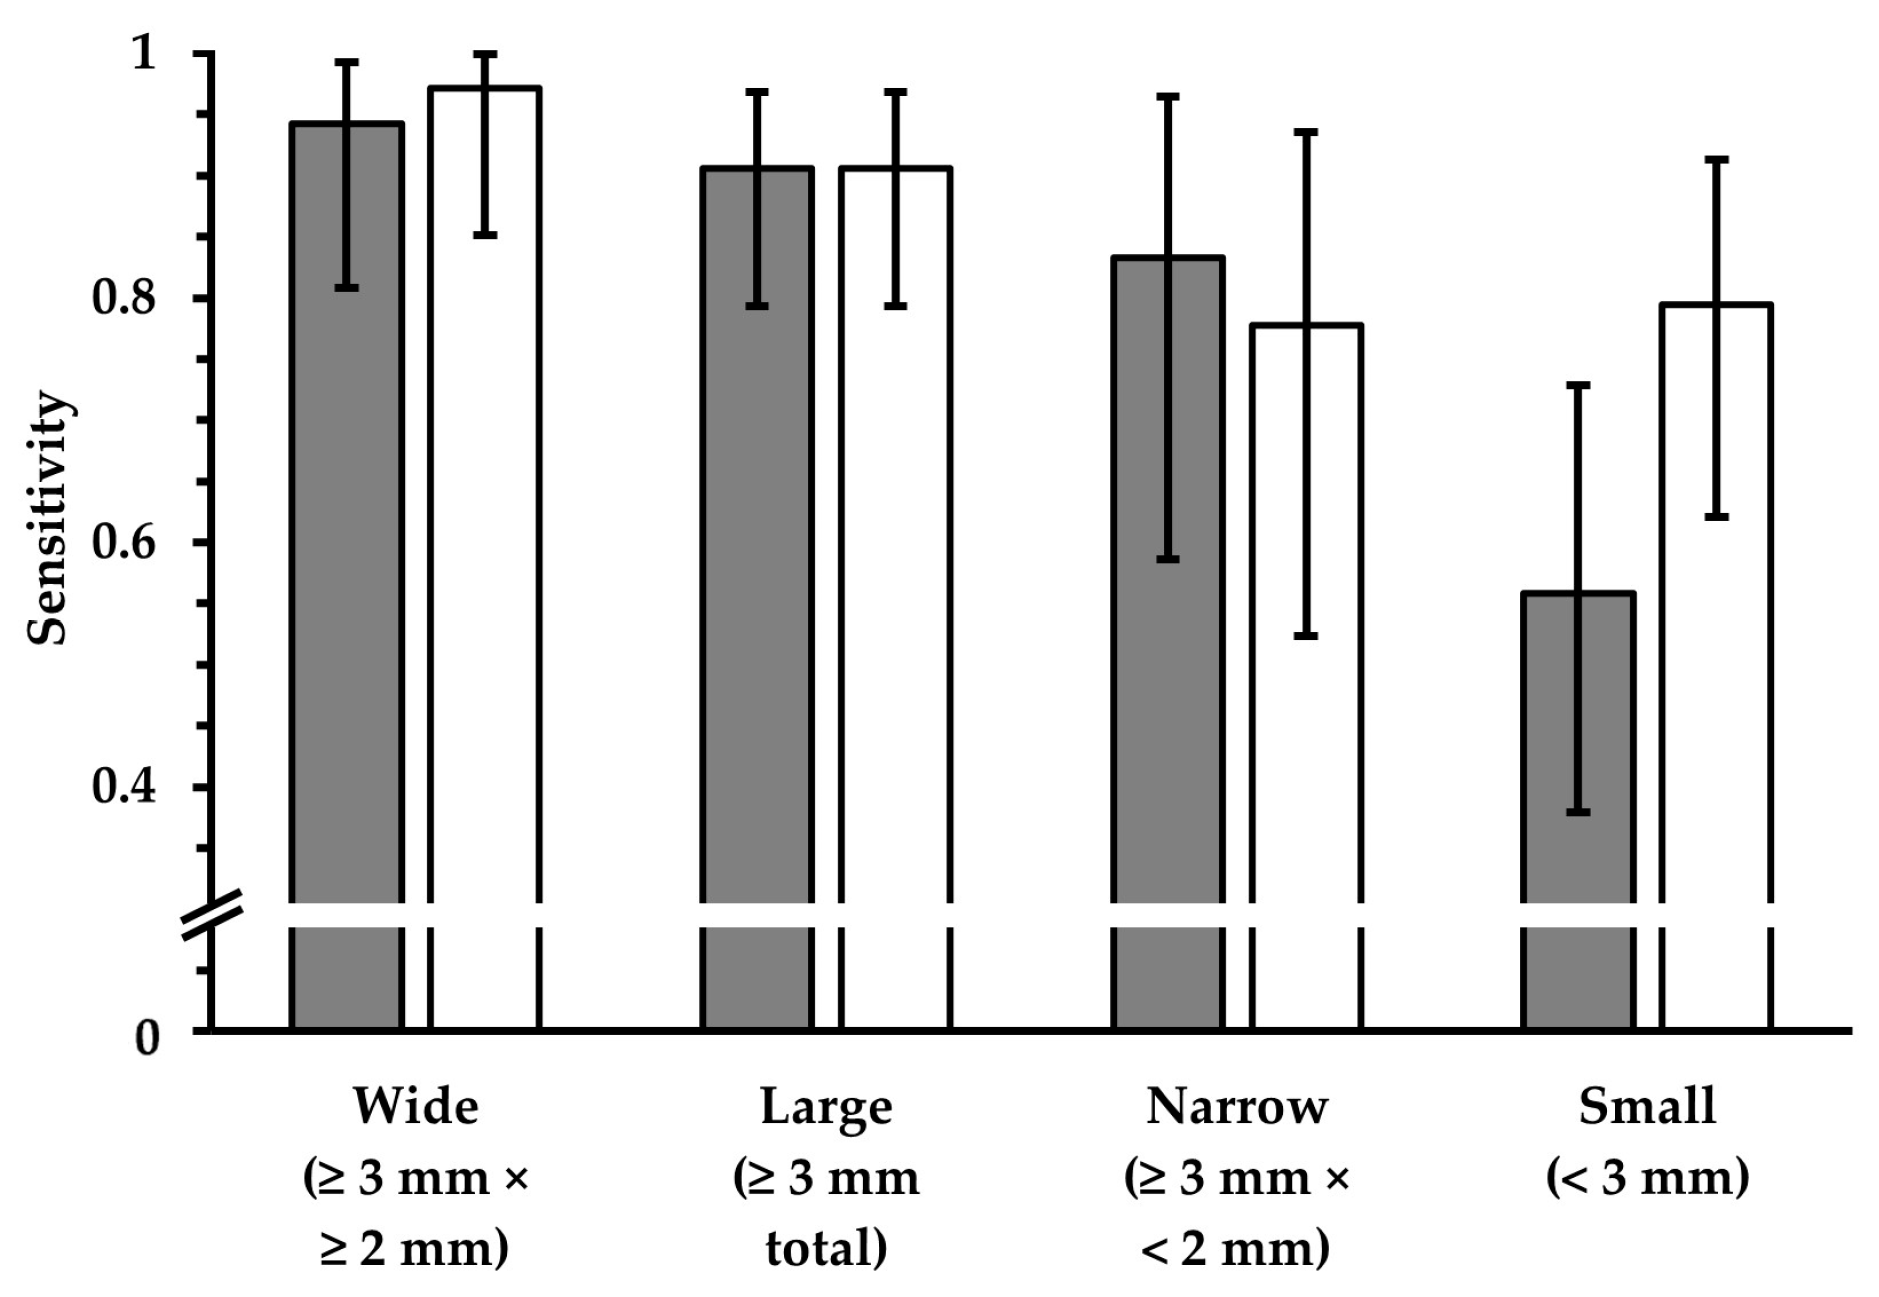

3.2. Lesion Detection

3.2.1. FLAIRUF Compared with FLAIR3Da

3.2.3. Dependence on Size and Location within FLAIRUF